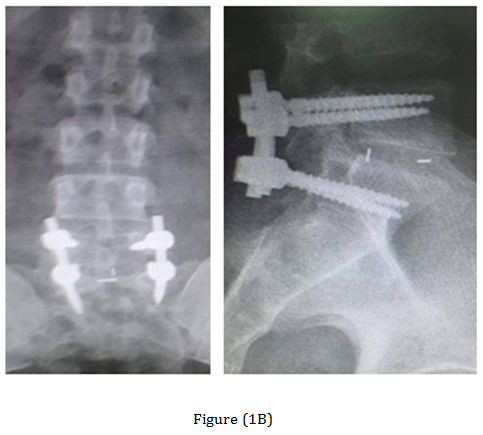

The post-operative Antero-posterior, lateral radiographs and dynamic views were used to assess the fusion mass at each level. The plain radiographs were obtained at 3 months, 6 months, 12 months, 18 months and 24 months to assess fusion status. Solid arthrodesis of the interbody space was confirmed by the presence of continuous bridging bone observed on the lateral radiographs, absence of lucencies around the cages, no cage migration or collapse and absence of halo around the screws. By Using this criteria, solid fusion was achieved in 18 patients (90%), whereas pseudarthrosis was documented in two patients. Low back and leg pain were completely resolved in 18 patients (90%) according to VAS (Table 1). All patients were rated minimal disability according to ODI (Table 2). The radiological outcome (Figure 1) showed solid fusion was achieved in 18 patients (90%), whereas pseudarthrosis was documented in two patients.

Figure 1 Case 3 with L.D.P L5-S1. (A) Preoperative radiograph anteroposterior and lateral views. (B) Preoperative MRI. (C) Post-operative radiographs anteroposterior and lateral views. (D) At the 18-months follow up anteroposterior and lateral views radiograph.